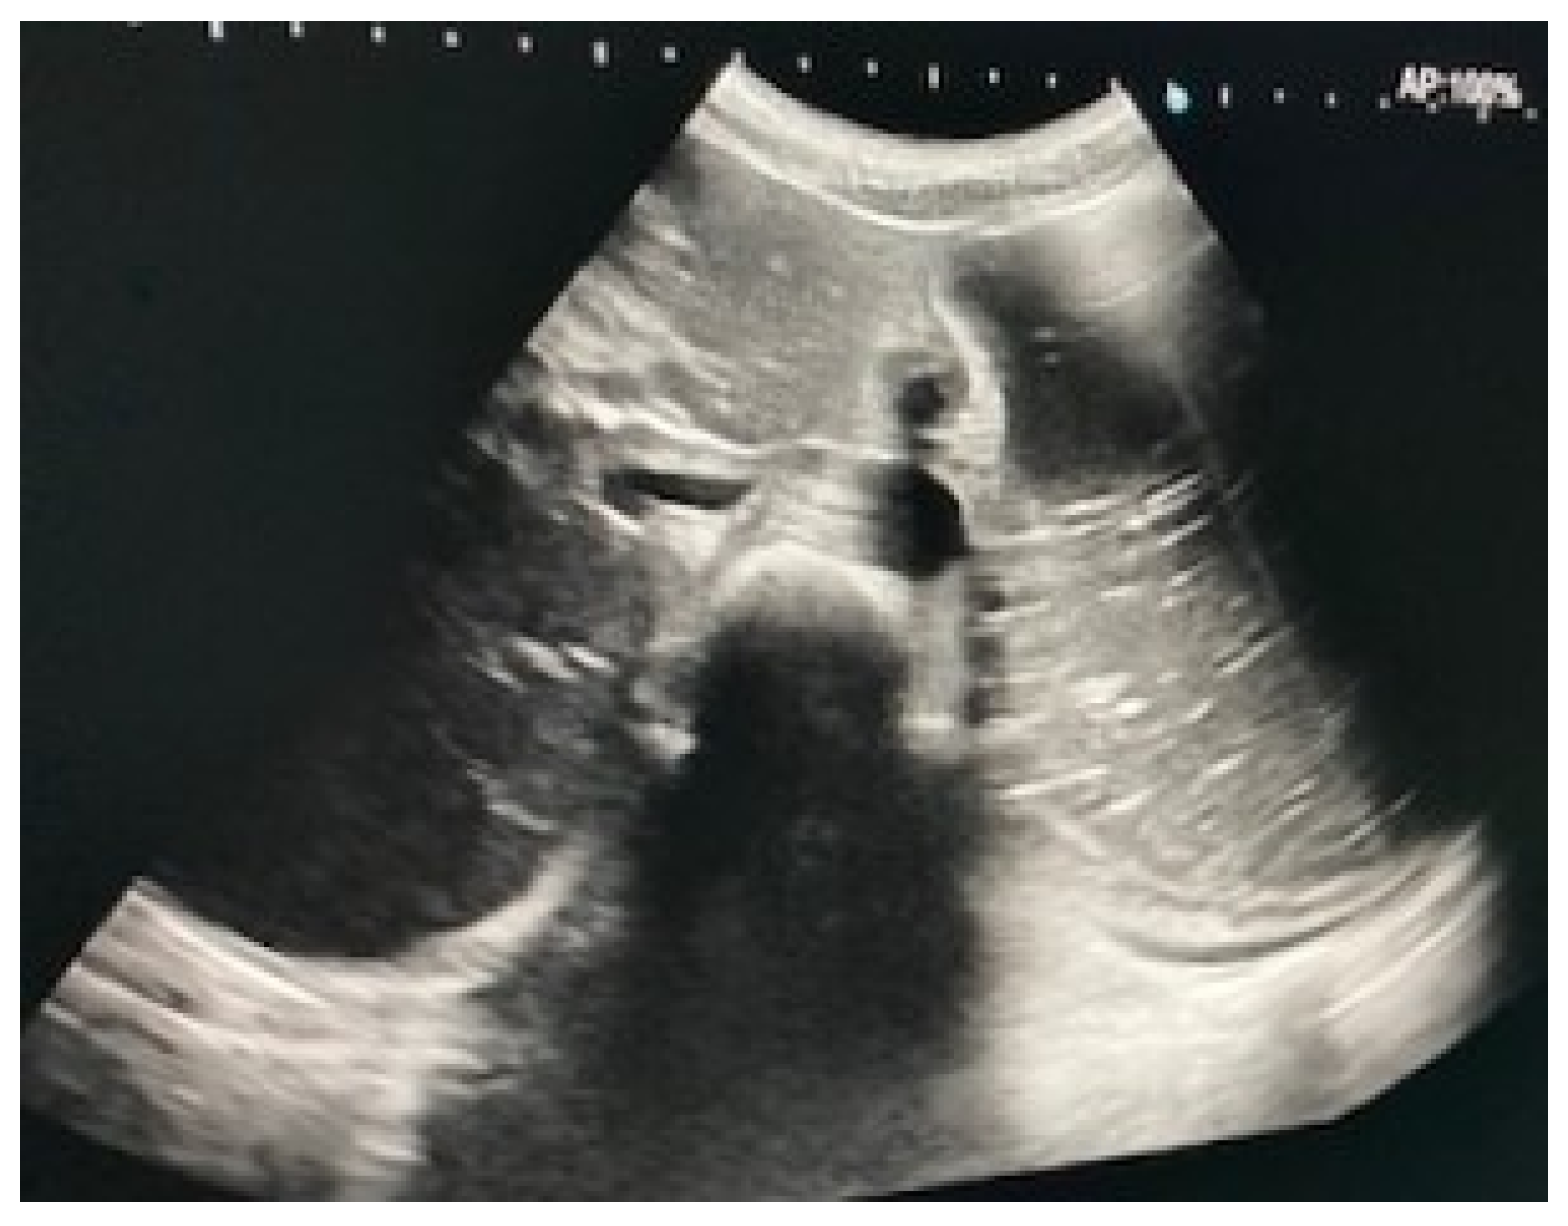

Immediate exploration of the abdomen was performed in the Emergency Department using X-rays, ultrasound, and a computed tomography (CT) scan of the abdomen. The abdominal ultrasound revealed an enlarged stomach (Figure 2), and the CT showed a vascular abnormality with a reduction of the aorto-mesenteric space of 21.6° and a distance (3.54 mm) obstructing the third portion of the duodenum, and partial left renal vein stenosis confirming the diagnosis of SMAS and Nutcracker syndrome (Figure 3).

Figure 2.

Abdominal ultrasound showing gastric distension.

Currently, the exact prevalence of vascular compression syndromes is unknown but is generally considered very rare, still poorly understood, and difficult to diagnose. Noninvasive tests such as standard ultrasound examination of the duodenum are insufficient for a positive diagnosis, but Doppler ultrasound offers detailed information concerning the venous and arterial flow, aorto-mesenteric angle, and distance enabling a quick and accurate diagnosis. Ultrasound is a sensitive method, and it has been shown to have a good correlation with CT [13].